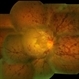

- Dengue maculopathy

- Dengue maculopathy healing phase.